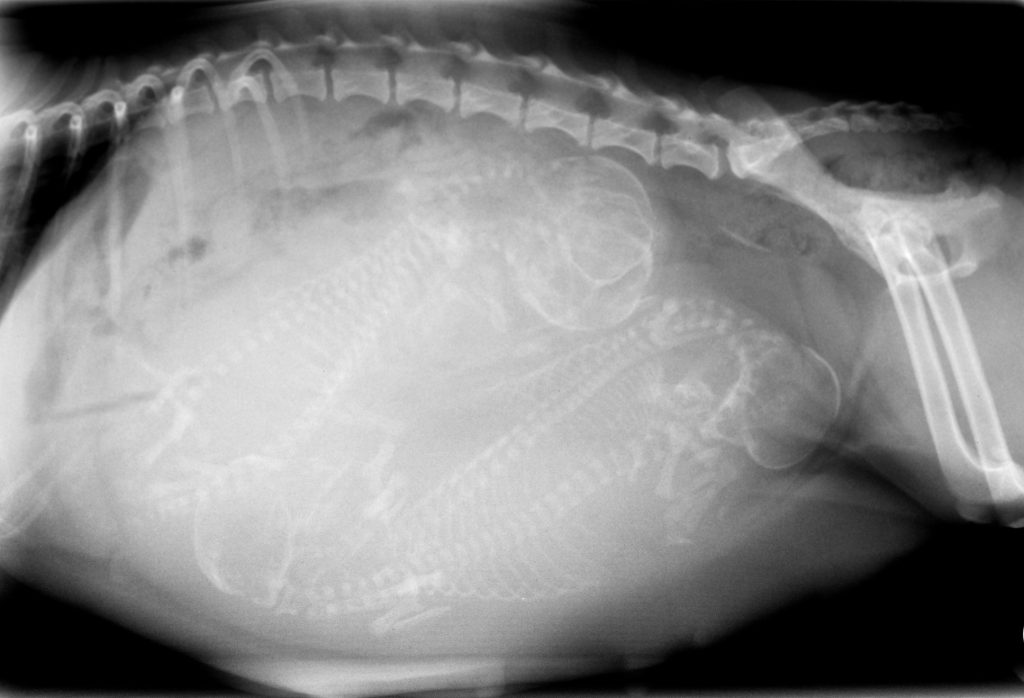

At Vets & Pets in Martinsburg, WV, we are proud to be on the cutting edge of medical technology. Radiology is a technique and diagnostic tool we use to look inside the body in an entirely non-invasive way. X-rays allow us to create images of all the body’s organs. In other words, the use of radiology gives us a view of the internal organs in your pet’s body that we otherwise could not see. It’s a valuable diagnostic tool that helps veterinarians detect and prevent illnesses.

The images produced by digital radiography are of much better quality than film radiographs and can be manipulated digitally, giving us the best possible radiographic information to help us diagnose your pets.

The use of radiology is safe, and our entire staff is highly trained. It is our goal to provide your pets with the highest level of medical care possible, and this is just one of the many ways we achieve that.